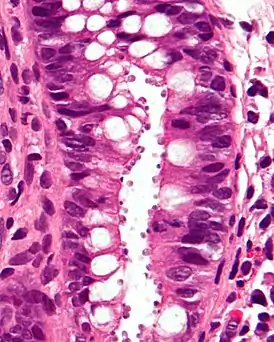

![]() Микрофотография гистологического среза кишечника, демонстрирующая заражённые клетки | |